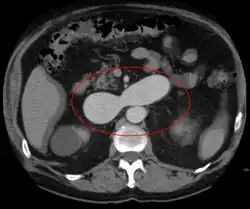

AVMs are diagnosed primarily by the following imaging methods:[12]

- Computed tomography (CT) scan is a noninvasive X-ray to view the anatomical structures within the brain to detect blood in or around the brain. A newer technology called CT angiography involves the injection of contrast into the blood stream to view the arteries of the brain. This type of test provides the best pictures of blood vessels through angiography and soft tissues through CT.

- Magnetic resonance imaging (MRI) scan is a noninvasive test, which uses a magnetic field and radio-frequency waves to give a detailed view of the soft tissues of the brain.

- Magnetic resonance angiography (MRA) – scans created using magnetic resonance imaging to specifically image the blood vessels and structures of the brain. A magnetic resonance angiogram can be an invasive procedure, involving the introduction of contrast dyes (e.g., gadolinium MR contrast agents) into the vasculature (circulatory system) of a patient using a catheter inserted into an artery and passed through the blood vessels to the brain. Once the catheter is in place, the contrast dye is injected into the bloodstream and the MR images are taken. Additionally or alternatively, flow-dependent or other contrast-free magnetic resonance imaging techniques can be used to determine the location and other properties of the vasculature.